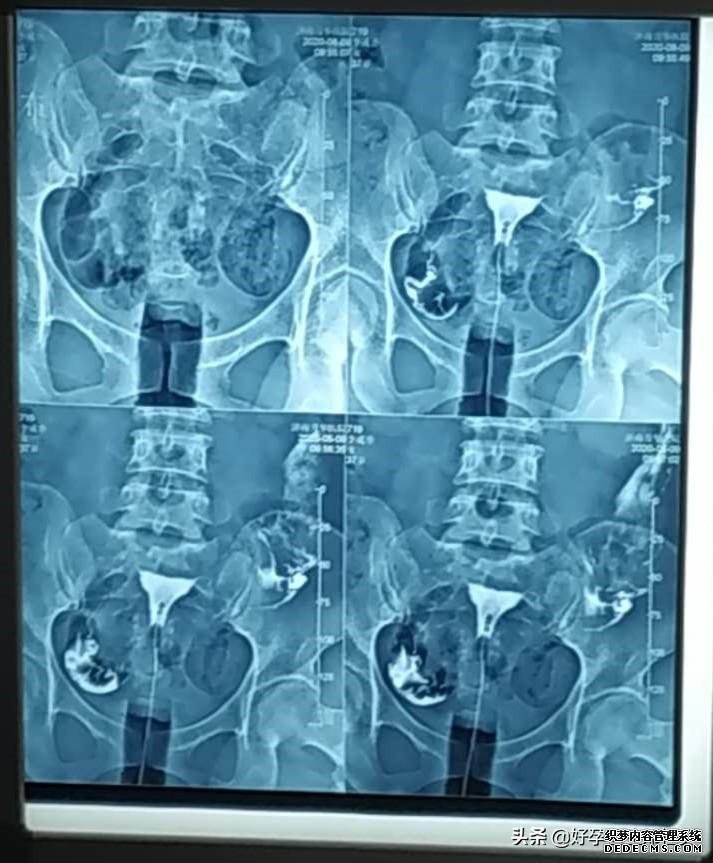

李姐今年33岁,已经备孕4年多了,上大学的时候做过一次人流,之后每次月经都会腰痛明显,但是因为年龄小,以为是痛经,也没有想过要去医院检查。2016年结婚开始备孕,做常规的孕前检查的时候,B超显示大量盆腔积液,附件增粗积水,在医生的建议下,又做了输卵管造影,结果显示双侧输卵管伞端粘连堵塞积水,盆腔炎。

子宫输卵管造影是通过导管向子宫和输卵管注入造影剂,通过X线来透视和摄片,然后根据造影剂在输卵管和盆腔内的造影情况分析输卵管通畅程度、阻塞的部位和宫腔的情况,是临床上很多不孕症女性常做的检查之一。

正常的子宫输卵管造影,应该是很容易就能把造影剂推进去,而且患者不会出现疼痛等明显症状。现在临床上的造影剂选用的都是碘水,常用76%的泛影葡胺,渗透压低,粘稠度低,可以扩散到输卵管的分泌物中,15分钟就能完成摄片,减少X线照射时间,注入半小时以内就能被身体吸收,对女性身体伤害小。